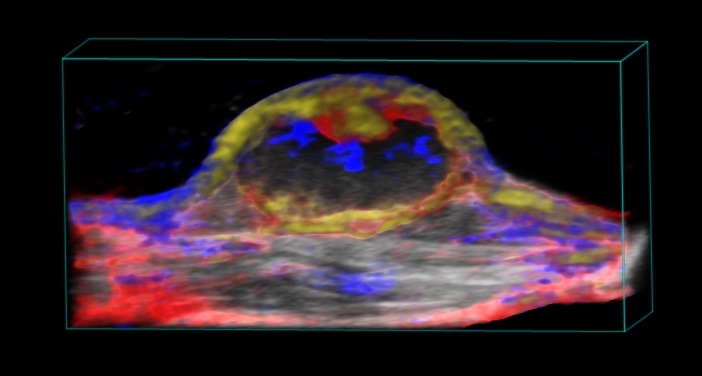

超音波による高い分解能・深度に加え、光イメージングの感度・特異性を同時に得ることが可能

フォトアコースティックによる機能的情報は、超音波のB-Mode画像上に統合・オーバーレイ表示できる為、解剖学的位置情報と共に解釈する事が可能です。

- 酸素飽和度・総ヘモグロビン量の算出(解剖学的B モード画像との統合表示、0.5Hz)

- 色素ラベリングによる特定細胞・分子の検出